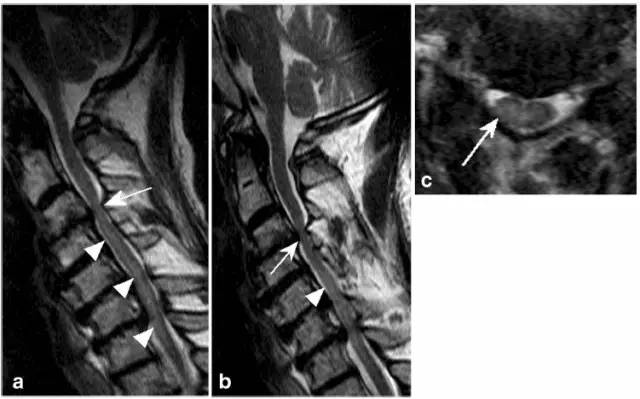

病例11:动脉受压导致脊髓缺血。